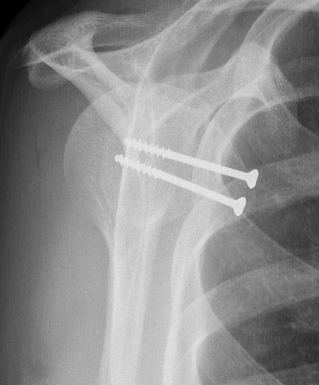

Fixation methods

- screw fixation +/- soft tissue washer

- suture anchor + screws

Screw fixation

Screw + soft tissue washer

Medial row anchors and lateral screws for missed lesser tuberosity avulsion in adolescent